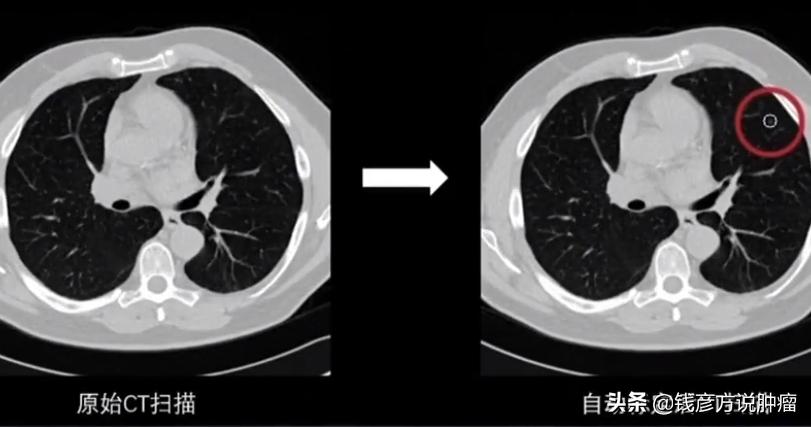

肺部结节是一种影像学的描述,是指肺部可见局灶性,类圆形密度增高的阴影。

她是从肺上发现的一个3厘米大的阴影,我们就叫结节,这个结节实际上分为几种结节,一个是实性结节、一个是磨玻璃结节,还有一个是混合性结节。

如果是磨玻璃结节它的发病率是很高的,有统计大概有60%-70%有可能是恶性的,另一个如果出现混合性结节,就是在磨玻璃结节的情况下有部分致密阴影,恶性程度在80%以上。